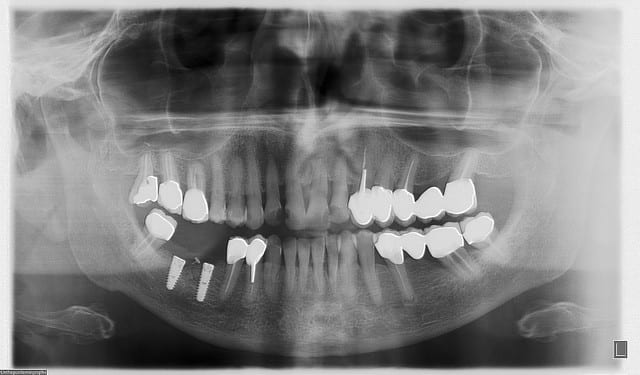

> en faisant une carotte osseuse aujourd'hui sur une crête mandibulaire, j'ai bien

> cru que j'avais coupé le nerf alvéolaire inférieur.

>

> je devais mettre un implant de 6mm là où il n'y avait que 3.5 à4mm d'os. le

> reste des spires devaient être laissées en supra crestal et une ROG verticale

> devait être réalisée avec des vis Fast et une mesh titane + recouvrement par une

> membrane de péricarde.

> bref, ce type d'intervention , je l'ai déjà fait plusieurs fois avec succès.

> seulement aujourd'hui, la tréphine apès avoir traversé la corticale est rentrée

> comme dans du beurre. j'ai été surpris car je faisait très attention. la

> patiente n'a absolument pas bronché d'un cil. quand j'ai retiré la carotte il y

> avait un truc mou accroché dessous; le V3 !

> on voit même sur la carotte la trace du nerf (photo)

> comme moi vous connaissez ce petit moment de monté d'adrénaline avec ce

> sentiment que la terre entière vient de vous tombé dessus? ben là j'ai eu ma

> petite goutte de sueur!

> au final j'ai replacé ma carotte et effectué ma ROG mais sans mettre mon

> implant.

> en plus c'était la loose complète, j'ai du retirer mes mesh titanes car le

> lambeau s'est déchiré juste en face de la vis qui les maintenait.

> j'ai revu la patiente en fin de soiré et finalement elle n'a pas de perte de

> sensibilité. attendons encore 72 heures pour être sure qu'il n'y ait pas de

> compression due à l'hématome.

> si c'est le cas ce sera corticothérapie retard à haute dose!

> là aussi, impossible de trouver du SYNACTHENE retard en IM. les dépôts n'en

> n'ont plus et aucun délais n'est donné. j'en ai heureusement trouvé ce soir chez

> un copain de mon pharmacien..

> y a des jours...

les couronnes ont été posées il y a peu de temps.